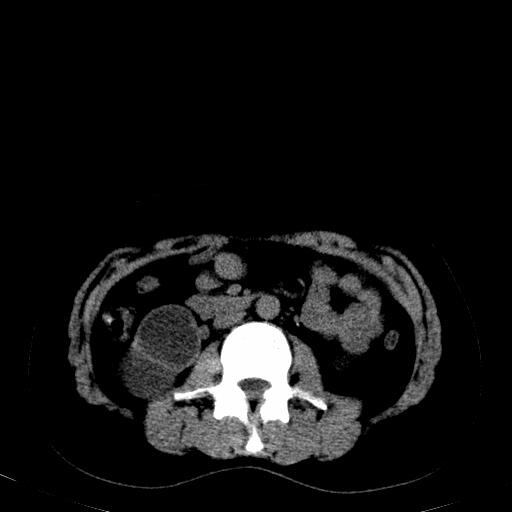

患者体检发现右肾体积增大,怀疑右肾积水

右肾重度积水,以肾盏积水明显,有分隔,上段输尿管轻度扩张,管壁增厚,考虑肾结核可能,请结合尿检查,胸部拍片排除肺结核。

右肾重度积水,建议ct向下扫描或逆行造影,左肾及左输尿管结石 .

患者尿常规正常,b超未发现明显结石,自身也无明显感觉异常。

请问多囊肾与肾积水怎么鉴别